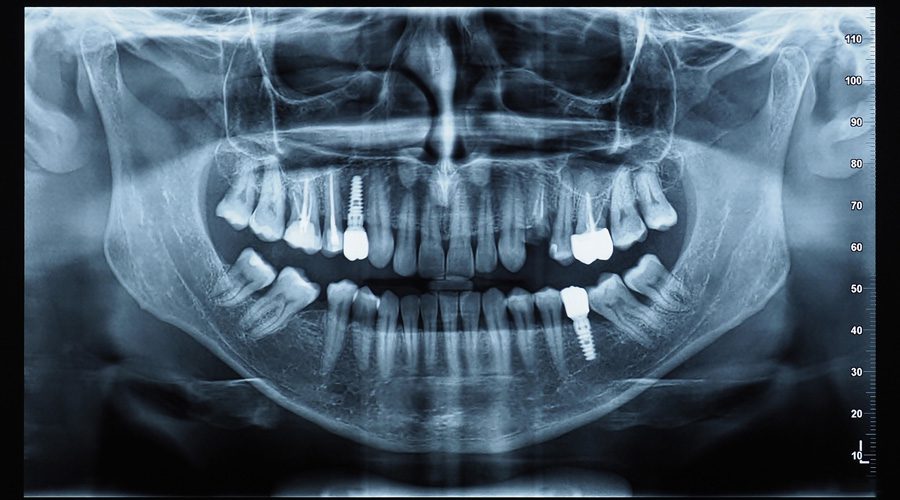

Consultation & 3D CT Scan

Often includes X-rays, 3D imaging, and Beam scans to evaluate your dental condition and to discuss the procedures that you might need.